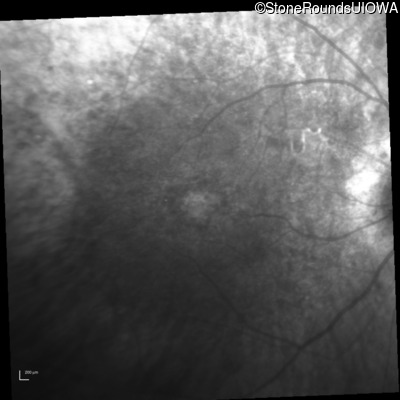

Infrared Fundus Photograph - Right - 20/80 +1

Exemplar